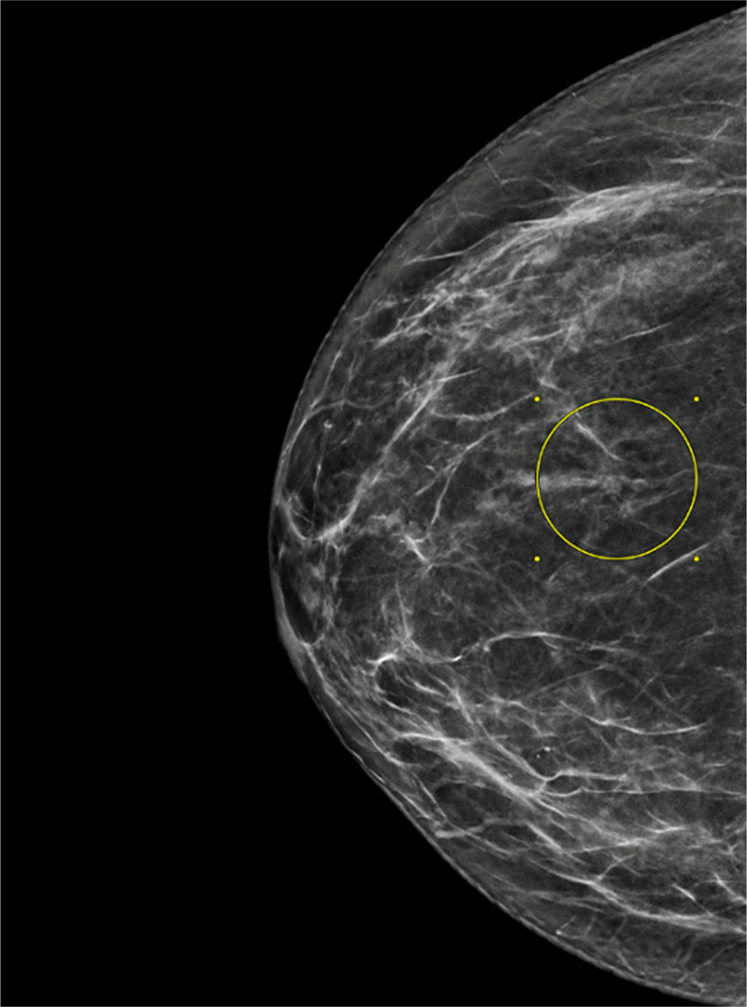

Fig. 1: The mammogram shows an area of architectural distortion consisting of lines radiating from a central point (circle). | Modern Pathology